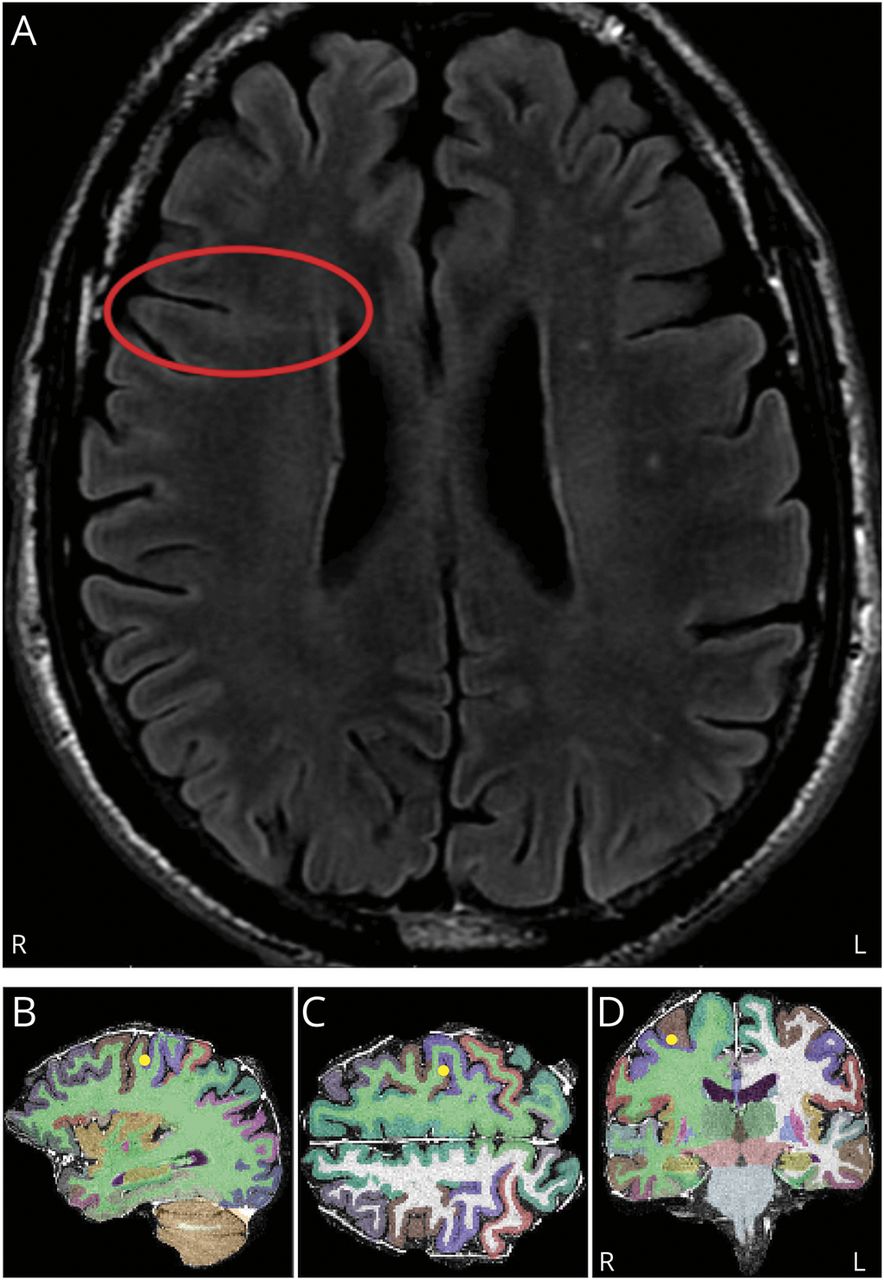

65岁男性,慢性耐药癫痫。脑电图视频监测显示癫痫发作表现为发作性撅嘴或“宪兵头”标志。MRI显示右侧额叶局灶性皮质发育不良(图1一个)。立体定向深度电极脑电图(立体脑电图)显示癫痫起源于右尾额中回的皮质沟(图1、B-D和2)。患者在切除癫痫发作区及皮质发育不良周围区域后无癫痫发作,术后9个月仍无癫痫发作。发作前撅嘴被描述为起源于额叶,特别是前扣带的癫痫发作的征兆1或者前岛叶皮层,2与患者癫痫发作无关的区域。意识到其他额叶区域是发作期撅嘴的共同网络的一部分可能对神经成像模式的解释很重要,如发作期单光子发射计算机断层扫描、PET和脑磁图,以及立体脑电图规划,特别是在mri阴性病例中。

术后病理证实局灶性皮质发育不良II型区域(A)。右尾额中回深度电极接触RPINS8定位,在矢状面(B)、轴向面(C)和冠状面(D)标记癫痫发作区。